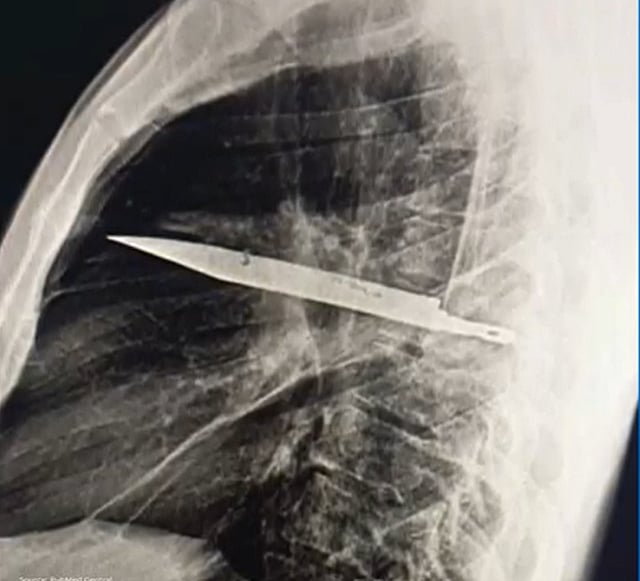

Doctors discover knife blade in man’s chest after 8 years

A 44-year-old man was found to have a knife blade lodged in his chest for nearly a decade, according to a recent report in PubMed Central, an electronic archive of biomedical and life sciences journal articles.

After visiting the general team at Muhimbili National Hospital, the patient received comprehensive treatment for the old stab wound. Initial imaging revealed that the knife blade had entered through his right shoulder area and remained embedded in his chest all these years.